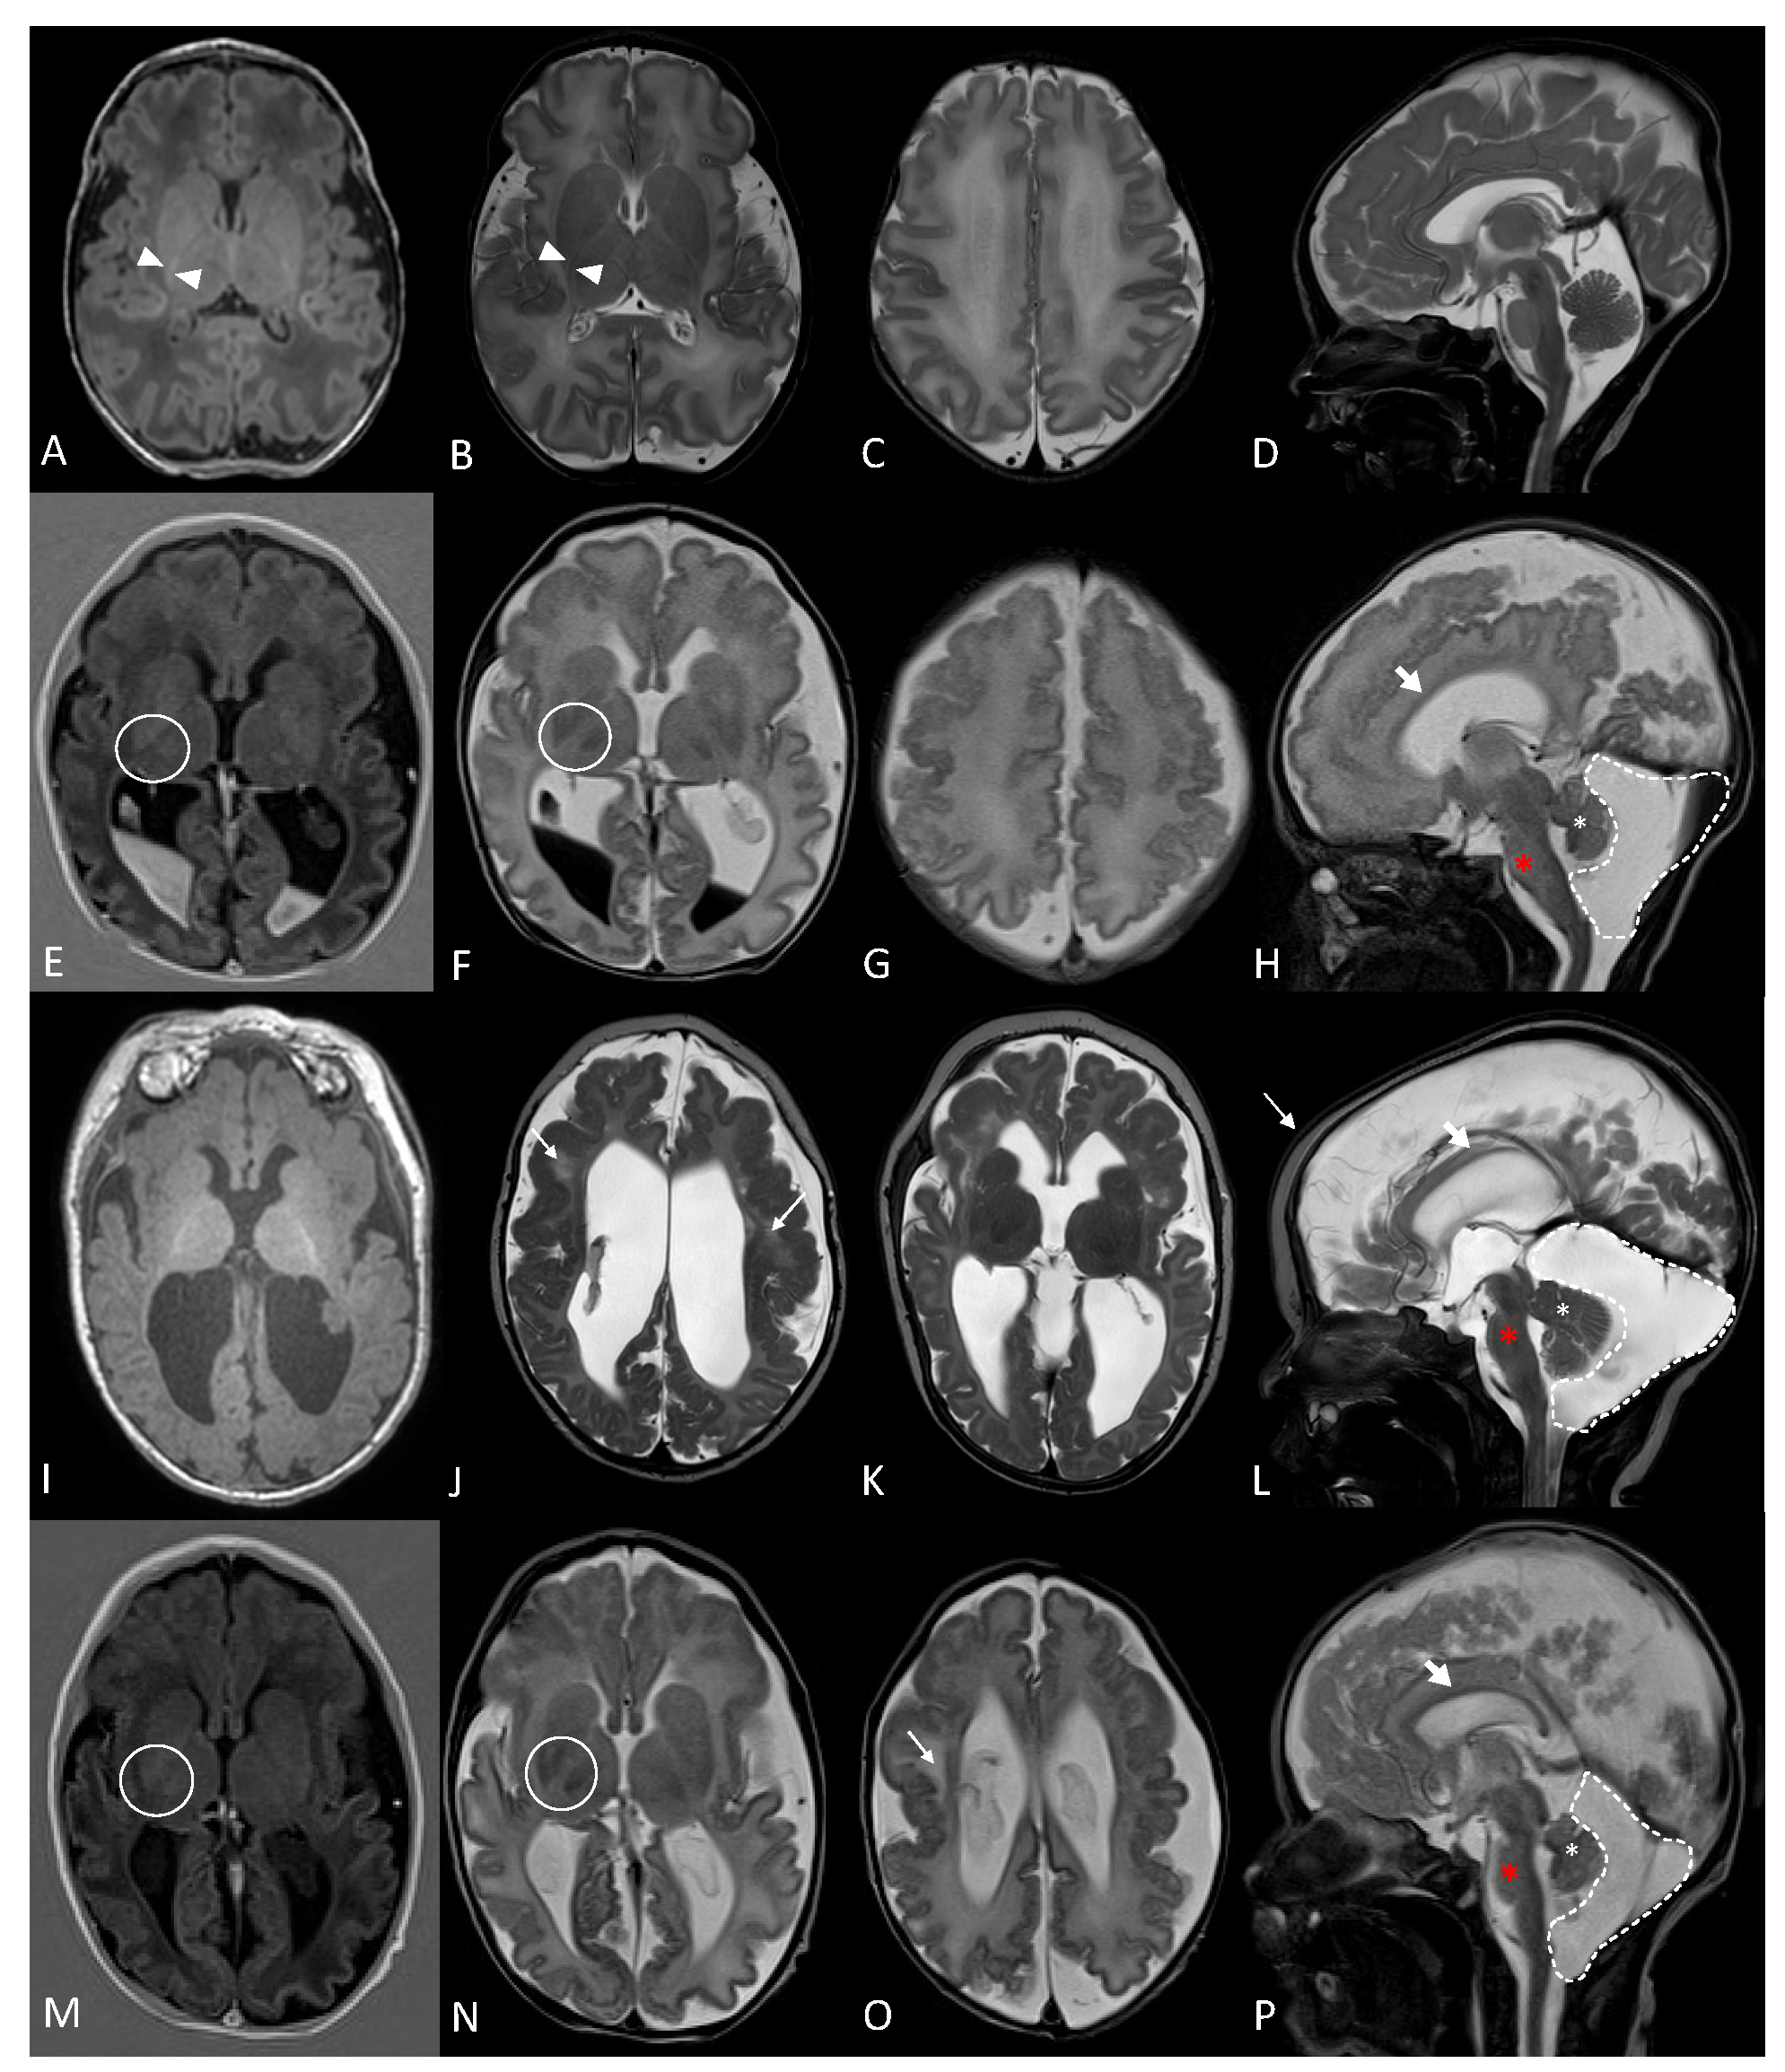

2. Case Report

2.1. Clinical Description